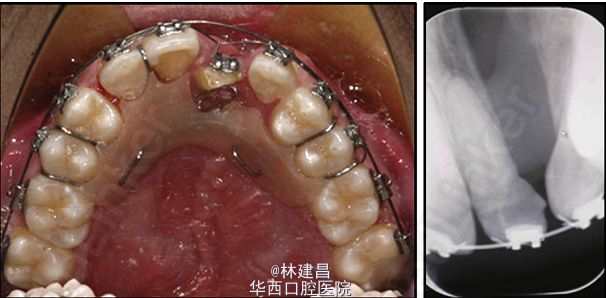

患者为18岁男性,面形凹,上颌骨发育不足,有一处重度牙槽突裂,因面部不美观,来正畸科求治。综合评价其病情后,为患者提供了手术和非手术两种方案,患者最终决定了非手术方案。此后患者的正畸治疗包括了扩弓、拔牙和牙周修复会诊。正畸治疗使用了新亚MBT托槽0.022x0.028(国产托槽也有好货!)配合微种植钉,排齐整平恢复I类磨牙关系。治疗完成1年后复诊。